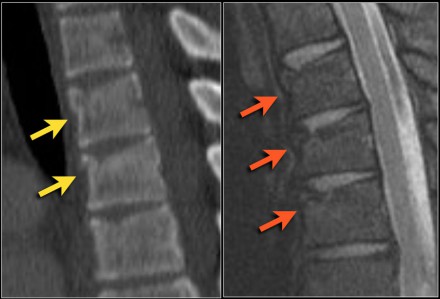

Look at the images.

What are the findings?

Then scroll to the next images.

The findings are:

- Vertebral bodies show marrow edema as a result of a fracture.

- Torn flaval ligament (yellow arrow).

- Fractures through the posterior elements (red arrows).

The TLICS-score is high, because there is distraction and injury to the PLC.